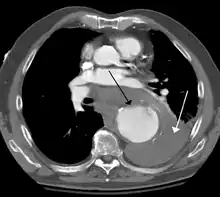

A thoracic aortic aneurysm is an aortic aneurysm that presents primarily in the thorax.

A thoracic aortic aneurysm is the "ballooning" of the upper aspect of the aorta, above the diaphragm. Untreated or unrecognized they can be fatal due to dissection or "popping" of the aneurysm leading to nearly instant death. Thoracic aneurysms are less common than an abdominal aortic aneurysm.[2] However, a syphilitic aneurysm is more likely to be a thoracic aortic aneurysm than an abdominal aortic aneurysm. This condition is commonly treated via a specialized multidisciplinary approach with both vascular surgeons and cardiac surgeons.

Thoracic aortic aneurysm is defined as a cross-sectional diameter exceeding the following cutoff:

- 4.5 cm in the United States[7]

- 4.0 cm in South Korea[8]

A diameter of 3.5 cm is generally considered dilated.[7] However, average values vary with age and size of the reference population, as well as different segments of the aorta.